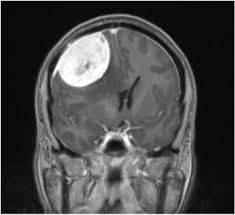

מנינגיומות מוחיות הן גידולים הגדלים לאט ומקורם בקרומי המוח. מרבית המנינגיומות (85%-90%) הן שפירות ובמיעוט המקרים (10-15%) הן בעלות דרגת אלימות גבוהה יותר ונוטות לחזור בשיעור גבוה, למרות טיפול.

מנינגיומות מצריכות טיפול כאשר הן גדלות במעקב או כאשר הן לוחצות על רקמת המוח וגורמות לסימפטומים נוירולוגיים (חולשה של יד או רגל, הפרעות בדיבור וכו') או כאשר הן מגיעות לממדים גדולים וגורמות לעליה בלחץ התוך-גולגלתי.

המעקב מתבצע לרוב באמצעות ביצוע MRI מוח וביקורות תקופתיות במרפאה. לעיתים מנינגיומות מאובחנות באופן אקראי (למשל ב- C.T מוח המבוצע בגלל חבלת ראש). במידה שהמטופל אינו סובל מתסמינים נוירולוגיים והגידול אינו גדל במעקב, אין צורך במתן טיפול מסוג כלשהו אלא במעקב הדמייתי בלבד. במידה שהוחלט כי צריך טיפול, קו הטיפול הראשון יהיה בד"כ ניתוח לכריתת המנינגיומה. המטרה בניתוח היא לכרות את כל הגידול ע"י הפרדה מיקרוכירורגית של הגידול מרקמת המוח והסרת הגידול עם הקרומים בהם הגידול נאחז ומהם נוצר. כריתת הגידול יכולה להתבצע ע"י ניתוח מסוג קרניוטומיה אשר במהלכו מתבצעת פתיחת גולגולת, זיהוי הגידול והפרדתו מהמוח וממבנים הסמוכים לגידול (צפו בסרט המדגים כריתת מנינגיומה ע'י פתיחת גולגולת) או במקרים מתאימים, בגישה אנדוסקופית דרך האף (צפו בסרט המדגים כריתת מנינגיומה מסוג טוברקולום בגישה אנדוסקופית). קרינה לרוב שמורה למקרים בהם לא ניתן לבצע ניתוח לכריתה שלמה של הגידול או במקרים של הישנות הגידול שאינם מתאימים לניתוח חוזר.